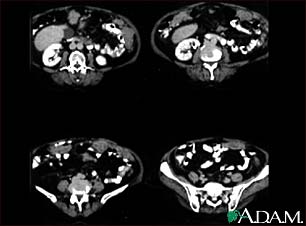

Peritoneal and ovarian cancer, CT scan

A CT scan series of the lower abdomen showing ovarian cancer that has metastasized (spread) to the peritoneum.